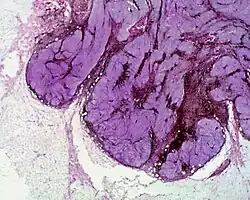

Histopathology

Cellular blue nevus Epithelioid blue nevus

Epithelioid blue nevus Malignant blue nevus